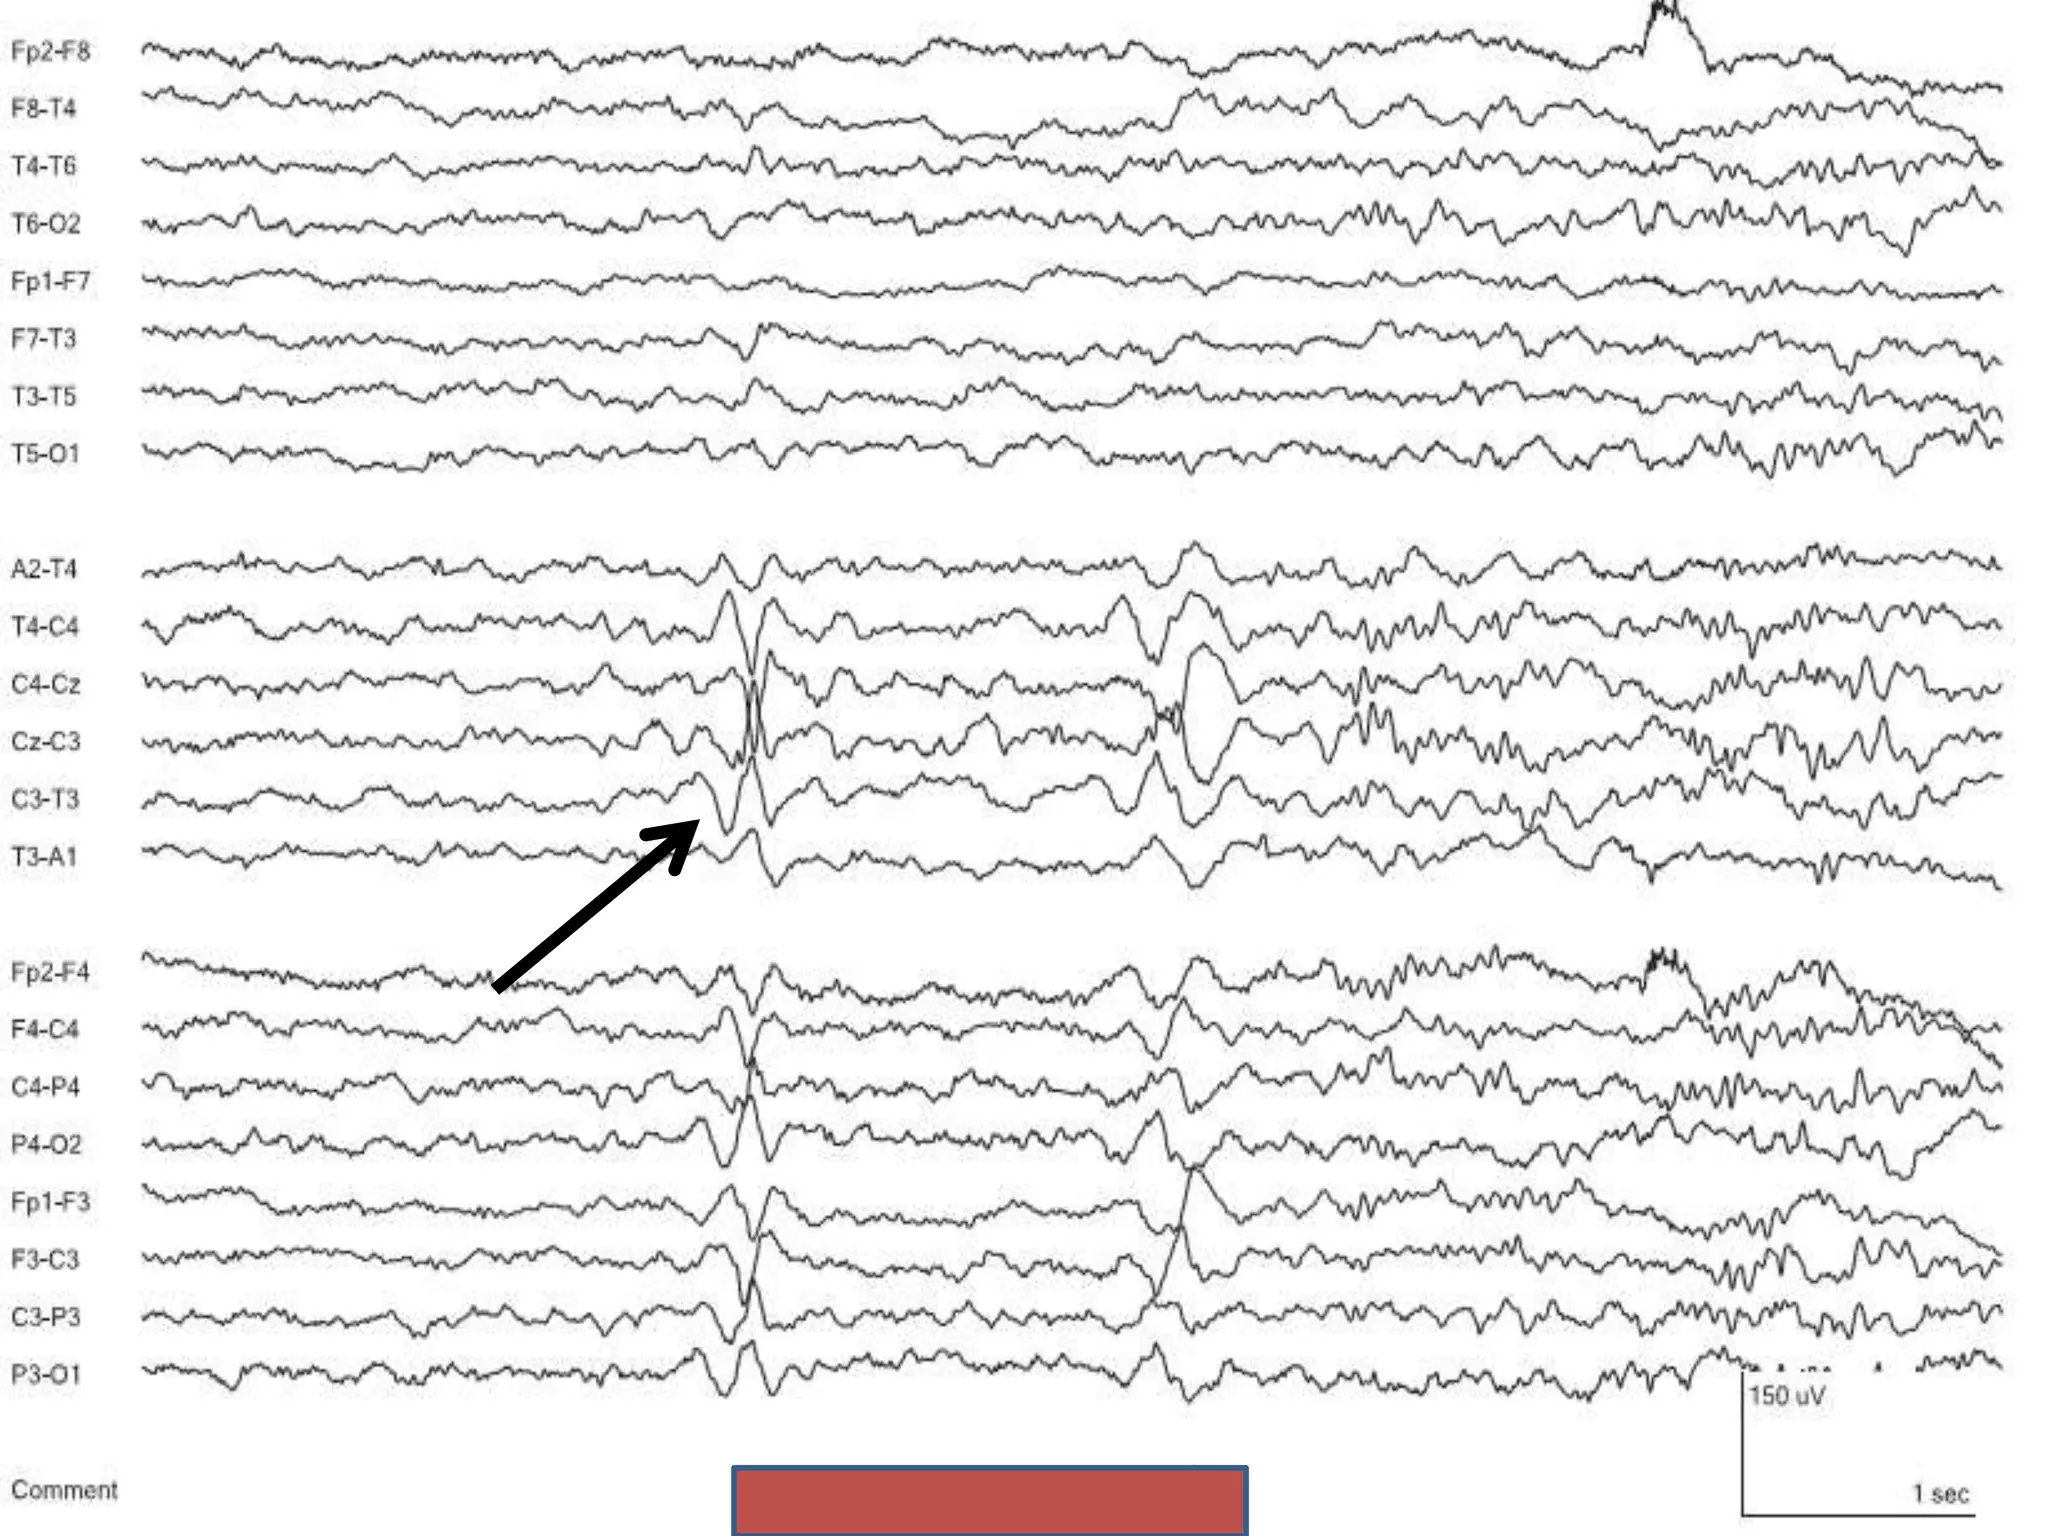

Rhythmic Temporal Theta of Drowsiness

(Psychomotor Variant)

• Trains of rhythmic theta waves 5-7Hz

• Duration 5-10sec

• Located in midtemporal region

• Often unilateral

• May be bisynchronous, with shifting asymmetry between sides

• Present in relaxed wakefulness and drowsiness

• Adolescents and adults

Rhythmic Temporal Thetaof Drowsiness (Psychomotor Variant) • Trains of rhythmic theta waves 5-7Hz • Duration 5-10sec • Located in midtemporal region • Often unilateral • May be bisynchronous, with shifting asymmetry between sides • Present in relaxed wakefulness and drowsiness • Adolescents and adults